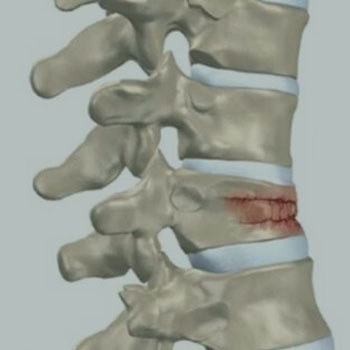

FRATURA

DOENÇA DEGENERATIVA DISCAL